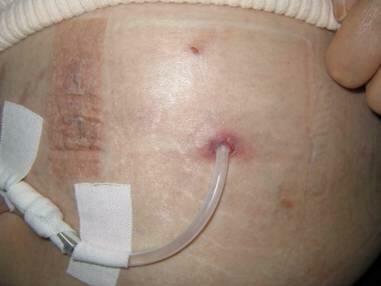

経過:Fig7に術後21日目の拡大像の所見を示す。

出口部周囲の上皮化は完成されているが、浸出がみられ全体に湿潤しており侵軟の状態である。

Fig8に一カ月後の像を示す。

aがカテーテルの過度の移動に伴い上皮が欠損し排膿が認められる。

bその二日後に治癒し上皮が再度おおっている像だが、湿潤し、侵軟が継続していることがわかる。

最初の出口部が完成する時期に侵軟の状態であると、辺縁の上皮化された皮膚の構造がもろく、傷つきやすい。

またいったん修復されても侵軟状態が継続しやすいこと示すと考えられた。

当初の上皮の形成を妨げた因子は心不全にともなう浮腫がコントロール不良な時期であったことが関与している。

経過:Fig9に術後21日目の肉眼像を示す。

腹部は膨満し浸軟で皮膚がむくみ、発疹が散在、出口部が膨隆している。

Fig10に同日の拡大所見を示す。

出口部は侵軟しており、肌理が不明瞭な状態である。

上皮化はされているが、今後、物理的な侵襲には容易に上皮の損傷をきたす可能性が考えられた。

腹水コントロールが困難な状況であり、このことが出口部の正常な形成を阻害し、侵軟な状態が今後も継続していくと考えられた。